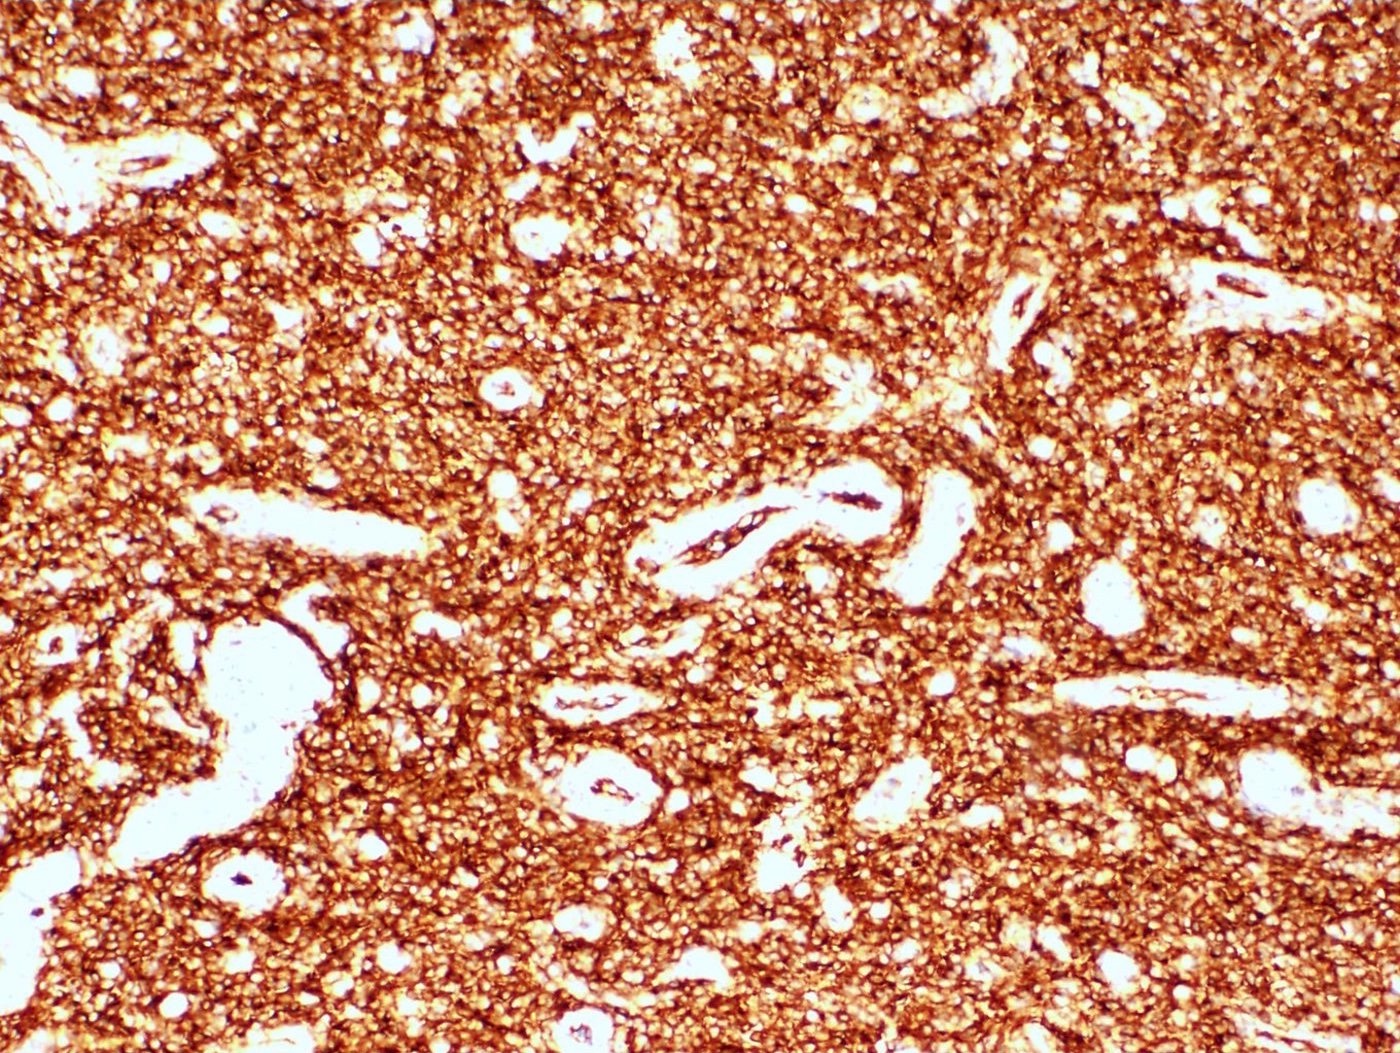

Microscopic (histologic) description

- Irregular cellular islands, forming permeative tongue-like pattern of myometrial invasion with frequent vascular invasion

- Monotonous oval to spindle cells with minimal cytologic atypia, vesicular chromatin and scant cytoplasm

- Tumor cells may whorl around delicate arteriolar type vessels, reminiscent of proliferative phase endometrial stroma

Microscopic (histologic) images

Contributed by Elizabeth Kertowidjojo, M.D., Ph.D., M.P.H. and Ayse Ayhan, M.D., Ph.D.

Positive stains

- CD10: sensitivity 91%, specificity 45% (Int J Gynecol Pathol 2018;37:372)

- IFITM1: sensitivity 83%, specificity 70% (Int J Gynecol Pathol 2018;37:372)

- WT1, ER (40 - 100%), PR (69 - 100%)

- Smooth muscle markers (SMA, desmin, caldesmon) often positive in areas of smooth muscle differentiation

- Sex cord markers (inhibin, calretinin, CD99, MelanA, WT1) may be positive in areas of sex cord differentiation